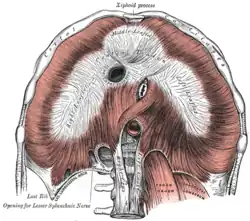

| Median arcuate ligament syndrome results from compression of the celiac artery by the median arcuate ligament. The median arcuate ligament is a fibrous arch formed by the left and right diaphragmatic crura, visible here on the underside of the diaphragm. | |

The median arcuate ligament is a ligament formed at the base of the diaphragm where the left and right diaphragmatic crura join near the 12th thoracic vertebra. This fibrous arch forms the anterior aspect of the aortic hiatus, through which the aorta, thoracic duct, and azygos vein pass. The median arcuate ligament usually comes into contact with the aorta above the branch point of the celiac artery. However, in up to one quarter of normal individuals, the median arcuate ligament passes in front of the celiac artery, compressing the celiac artery and nearby structures such as the celiac ganglia.[2] In some of these individuals, this compression is pathologic and leads to the median arcuate ligament syndrome.[2]